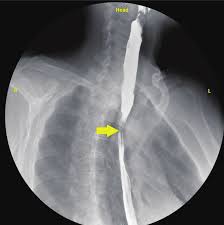

Patient presented with progressive dysphagia predominantly for solid food. Barium swallow study showed smooth narrowing in the distal esophagus with proximal dilatation, suggestive of benign esophageal stricture. No shouldering or irregular margins seen.

Image Description (Peptic Stricture): A barium swallow showing a smooth, tapered, focal area of narrowing in the distal esophagus, commonly caused by chronic acid reflux.